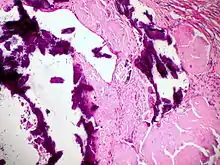

Ausgeprägte Amyloidablagerungen (homogen rosa) in einem Lymphknoten, H&E.

Amyloidablagerungen in den Gefäßwänden, H&E.

Dystrophische Verkalkung (violett) bei Lymphknotenamyloidose, H&E.